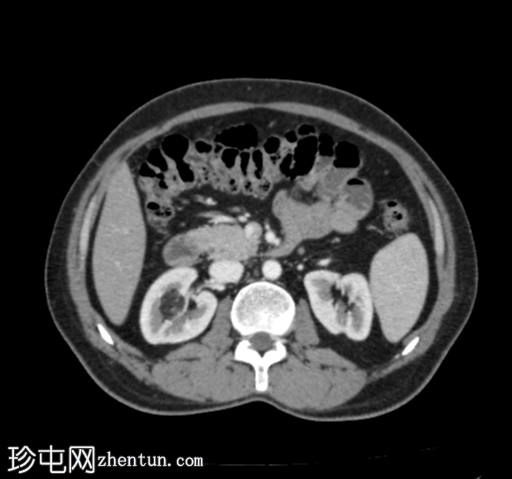

CT

轴位增强扫描(门静脉期)

CT扫描显示右肾上半部可见一部分边界清晰的肿块,其密度成分包含软组织和脂肪。

其余腹腔脏器未见明显异常。

可见累及L4椎体的血管瘤。

目前的CT

影像

学表现为右侧肾血管平滑肌脂肪瘤,无内部出血。